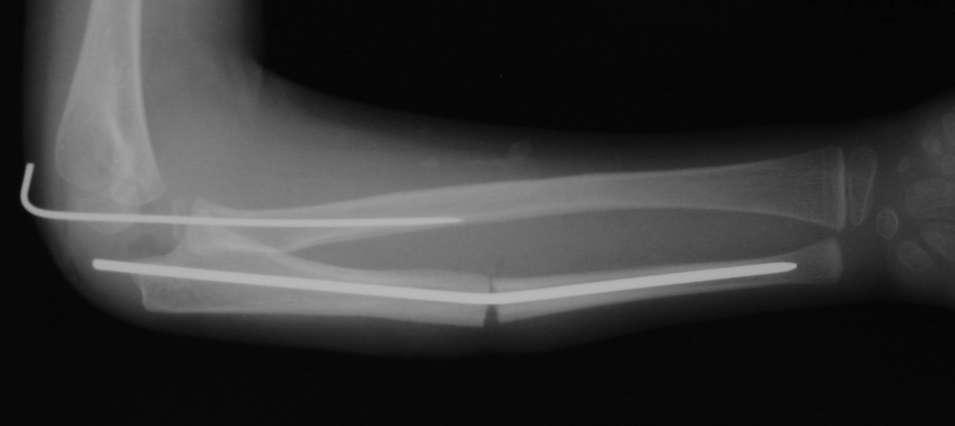

Иллюстрация к лечению застарелого повреждения Монтеджиа

Пациентка клиники детской травматологии ЦИТО

оперировали подобный случай около 6 мес назад. Отличие только в одном- давность травмы была до 2х лет. Использовали методику описанную в "Pediatric fractures and dislocations" Lutz von Laer, M.D.

Артротомия, иссечение рубцов, остатков кольцевидной связки. На проксимальный отдел локтевой кости стержневой аппарат (рекомендуют

Compact II выпущеный Stryker Howmedica, но за неименеем...), остеотомия проксимального отдела локтевой кости, вправление головки лучевой кости, замыкание аппарата, проверка стабильности головки

лучевой кости в движении, ушивание без пластики кольцевидной связки.

Данную методику применили впервые. После артролиза очевидная нестабильность головки луча. После остеотомии локтевой, вправления и

стабилизации аппарата головка луча при движениях на месте. Первые впечатления- "Либо чудо,либо фокус" (с) :))

1 подвывих головки лучевой кости в положении супинации - через 2 недели после операции- под ЭОП: аппарат разблокирован, повторное вправление головки, стабилизация аппарата.

2 По снятии аппарата через 2 мес после операции рефрактура в месте остеотомии(на фоне активного ротационного движения)- под контролем ЭОП выполнен

интрамедуллярный остеосинтез TEN. Положение головки луча стабильное.